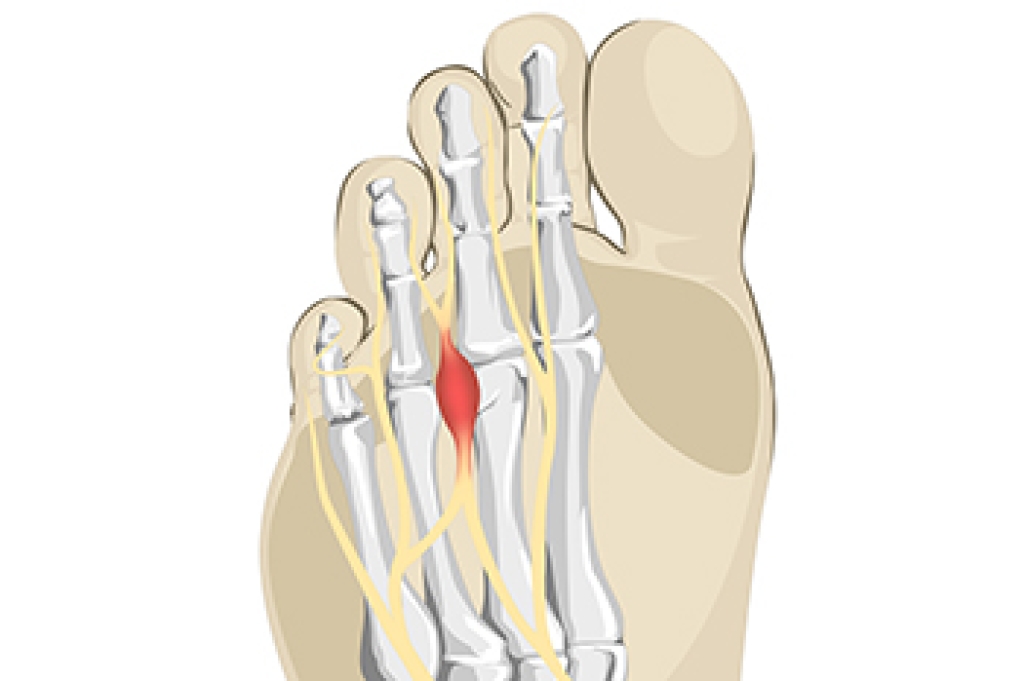

Multiwave Locked System (MLS) Laser Therapy is a patented, FDA-cleared technology that helps relieve pain and inflammation from a number of podiatric conditions, including:

- Neuromas